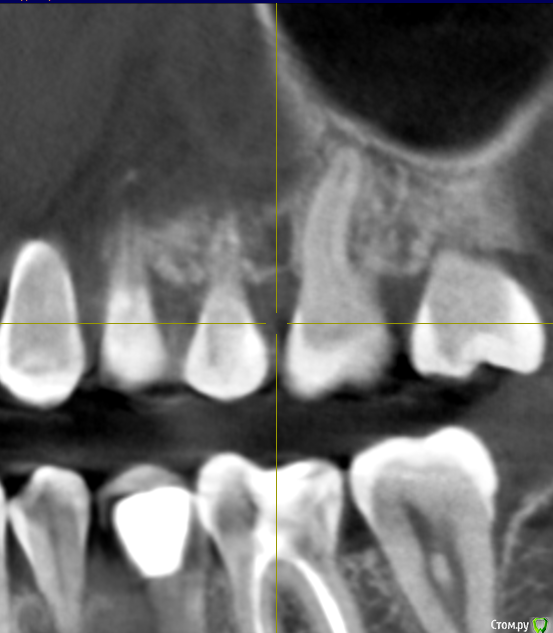

Добрый день! Два месяца назад началась моя история с зубами. Беспокоили дикие боли в зубах, как при пульпите, в 4-ке и 5-ке. Сделано было несколько прицельных и рентгеновских снимков, которые ничего не показали. Обошла пять стоматологов, никто проблем не находил, отправляли к лору или неврологу. КТ никто сделать не предложил, к сожалению. Было принято решение совместно с шестым! стоматологом депульпировать эти два зуба. При удалении нервов стоматолог сказал, что нервов уже почти нет и в 4, и в 5, сказал, что у меня хронический периодонтит, а в 4-ке стоматолог увидела на снимке (когда проверяла каналы после лечения) наружную резорбцию корня. В 5-ку поставили сразу постоянную пломбу, в 4-ке сейчас стоит временная (материал МТА). Но боль в 4-ке осталась, она не такая конечно сильная, как была, но ноющая, усиливается после горячего, после еды, в основном. И над зубом есть свищ, он не беспокоит и не болит при надавливании (стоматолог говорит, что это материал под десной, из-за резорбции) Врач говорит, что все пройдет, и через 2 месяца ставим постоянную пломбу, но болит уже месяц. Я сама сделала КТ, очень прошу вас посмотреть и подсказать, как действовать дальше? Может проще удалить этот зуб и поставить имплантат?